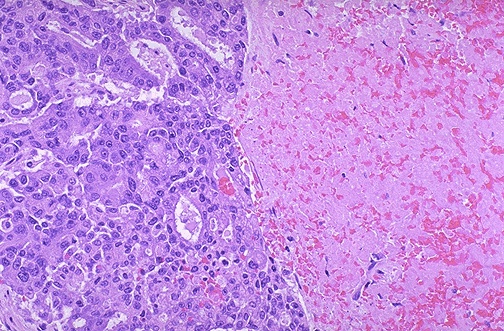

| At the right is an area of necrosis and hemorrhage in this hepatocellular carcinoma. Liver cell carcinomas are very prone to necrosis and hemorrhage. In fact, hemorrhage from such an hepatocellular carcinoma at the liver capsule may lead to hemoperitoneum. |